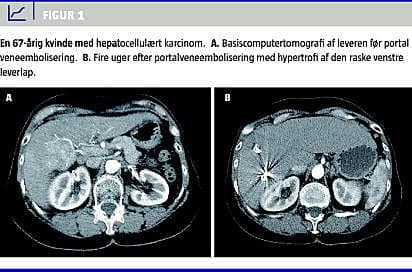

Den optimale behandling af patienter med malign sygdom i leveren er kurativt intenderet radikal resektion. Ved resektion skal der efterlades mindst 25% fungerende levervæv, for at leverinsufficiens kan undgås [1]. Selv om leveren har stor regenerationskapacitet, som påvist i dyreeksperimentelle studier, hvor man har reseceret leveren op til ni gange, uden at regenerationskapaciteten er blevet kompromitteret [1], vil den fremtidige leverrest (FLR) af og til være for lille til at kunne klare sufficient leverfunktion. Portal vene-embolisering (PVE) er en interventionsradiologisk behandling, der har til formål præoperativt at embolisere det portale kredsløb til leversegmenter med malignitet og derved ophæve den portale gennemblødning i disse og omdirigere den portale gennemstrømning til de raske og ikkeemboliserede segmenter. Herved opnås der hyperperfusion gennem den resterende uafficerede del af leveren (som regel venstre leverlap, segment 1, 2 og 3), og der opnås hypertrofi og øget volumen på omkring 30% af denne FLR [2, 3] (Figur 1 A + B). Dette muliggør ekstensiv leverresektion hos patienter, hvor der ellers var kontraindikation pga. af for lille leverrest [1]. PVE opfølges almindeligvis 3-6 uger senere af kirurgisk udvidet leverresektion af de tumorafficerede leversegmenter (almindeligvis højresidig hemihepatektomi med eller uden resektion af segment 4) på et tidspunkt, hvor den hypertrofierede leverlap har tilstrækkelig kapacitet til en sufficient leverfunktion [3]. Efter leverresektionen vil FLR yderligere kunne hypertrofiere med op til 38% [3] (Figur 2 A + B). PVE blev introduceret af Kinoshita et al i 1986 [4].